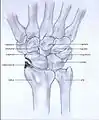

- Stage II: the osteoarthritis is localized in the entire radioscaphoid joint.

Stage II

The surgical options for stage II and III wrist osteoarthritis are excision of some of the bones with or without fusion (arthrodesis) of the others. The idea is to try to alleviate pain while maintaining some wrist motion.

One technique is to remove one row of carpal bones. The bones closer to the forearm (proximal) are removed: scaphoid, lunate, and triquetrum.[14] It is important that the radioscaphocapitate ligament is left intact, because if the ligament is not preserved the capitate bone will translate to the ulnar side of the wrist and move away from the distal radius.[1][15]

The new articulation of the capitate with the lunate fossa of the distal radius is not as congruent as the former scaphoid-lunate-radius joint.[16][17] This and other issues contribute to potential to develop arthritis over the years. In part based on these concerns, some surgeon prefer to maintain the lunate in patients younger than 40 years proximal row carpectomy. [6][18]

A surgery called four-corner arthrodesis is an option.[6] The capitate, lunate, hamate and triquetrum are fused together in this procedure and the scaphoid is excised.[1][14] Before the arthrodesis is executed, the lunate must be reduced out of DISI position.[14] Because the radiolunate joint is typically preserved in stage II SLAC and SNAC wrists, this joint can be the only remaining joint of the proximal wrist. Both procedures are often combined with wrist denervation, as described in the text of treatment stage I.